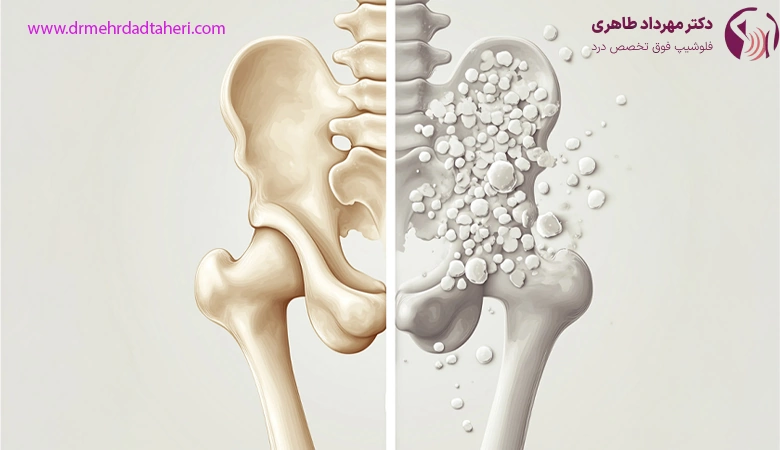

پوکی استخوان یک اختلال اسکلتی است که بیشتر در سنین بالا بروز میکند و ویژگی آن کاهش استحکام استخوان هاست. این بیماری به تدریج و بدون درد در ابتدا پیشرفت میکند و موجب ضعیف شدن استخوانها میشود تا جایی که حتی یک ضربه یا فشار خفیف میتواند منجر به شکستگی استخوان گردد. به همین دلیل، شناخت این بیماری و انجام اقدامات پیشگیرانه برای جلوگیری از پیشرفت آن بسیار مهم است. در این مقاله، به بررسی پوکی استخوان، علائم، علل، روشهای تشخیص، پیشگیری، درمان و نکات ضروری درباره این بیماری پرداخته میشود.

پوکی استخوان یا استئوپروز، به وضعیتی اطلاق میشود که در آن تراکم و کیفیت استخوانها به طور قابل توجهی کاهش مییابد. این کاهش تراکم باعث میشود استخوانها ضعیف و شکننده شوند و خطر شکستگیهای استخوانی افزایش یابد. پوکی استخوان در افراد مسن بیشتر مشاهده میشود، اما میتواند در هر سنی رخ دهد. جهت درمان پوکی استخوان میتوانید به دکتر مهرداد طاهری، بهترین متخصص درد در تهران مراجعه کنید.

پوکی استخوان یک بیماری شایع و خطرناک است که میتواند به کاهش کیفیت زندگی و افزایش خطر شکستگیها منجر شود. پیشگیری از این بیماری با رعایت سبک زندگی سالم، رژیم غذایی مناسب، و ورزش منظم امکانپذیر است. همچنین، در صورت تشخیص زودهنگام و درمان مناسب، میتوان از پیشرفت بیماری جلوگیری کرده و کیفیت زندگی فرد را بهبود بخشید. اگر شما یا یکی از اعضای خانوادهتان با علائم پوکی استخوان روبرو هستید، حتماً به پزشک متخصص مراجعه کنید تا تشخیص و درمان لازم انجام شود.